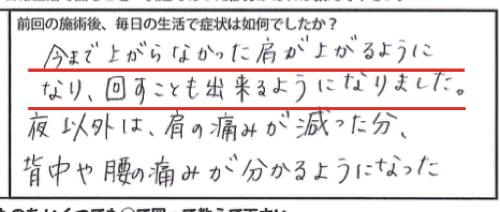

そして1週間後に再度ご来院頂いた際はこんなコメントをいただきました。

今まで上がらなかった肩が上がるようになり

回すことも出来るようになりました。

夜以外は、肩の痛みが減った分

背中や腰の痛みが分かるようになった。

腕は上がるものの仕事を終えて帰宅し

寝るときにはまた肩に痛みが出てしますそうです。